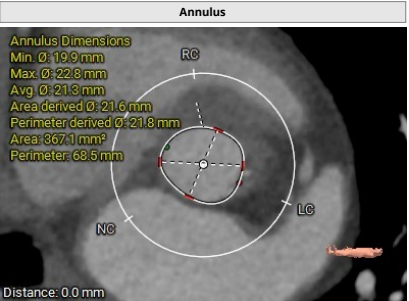

临床团队同时使用了Tavigator™进行术前影像学评估,配合医生手工描点评估。

主动脉瓣瓣环及其它基本平面测量

患者为71岁女性。瓣环圆化直径21.8mm,Type0型二叶瓣,瓣叶增厚轻度钙化。左侧冠脉开口高度13.1mm,右侧冠脉开口高度13.8mm,并且STJ高度可以达到22.3mm。投照角度推荐LAO8度/CRA8度。可行18mm球囊前扩,考虑到环上锚定,推荐0位植入Xcor™-23瓣膜,酌情后扩。